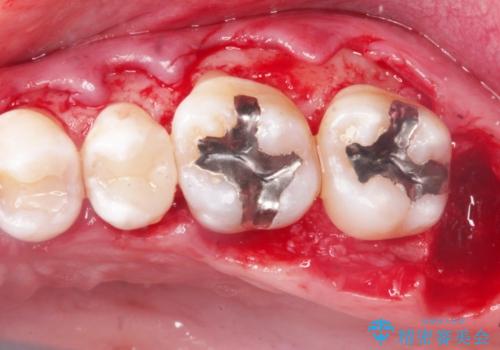

2. 縁下歯石のクリーニングの治療中

2.